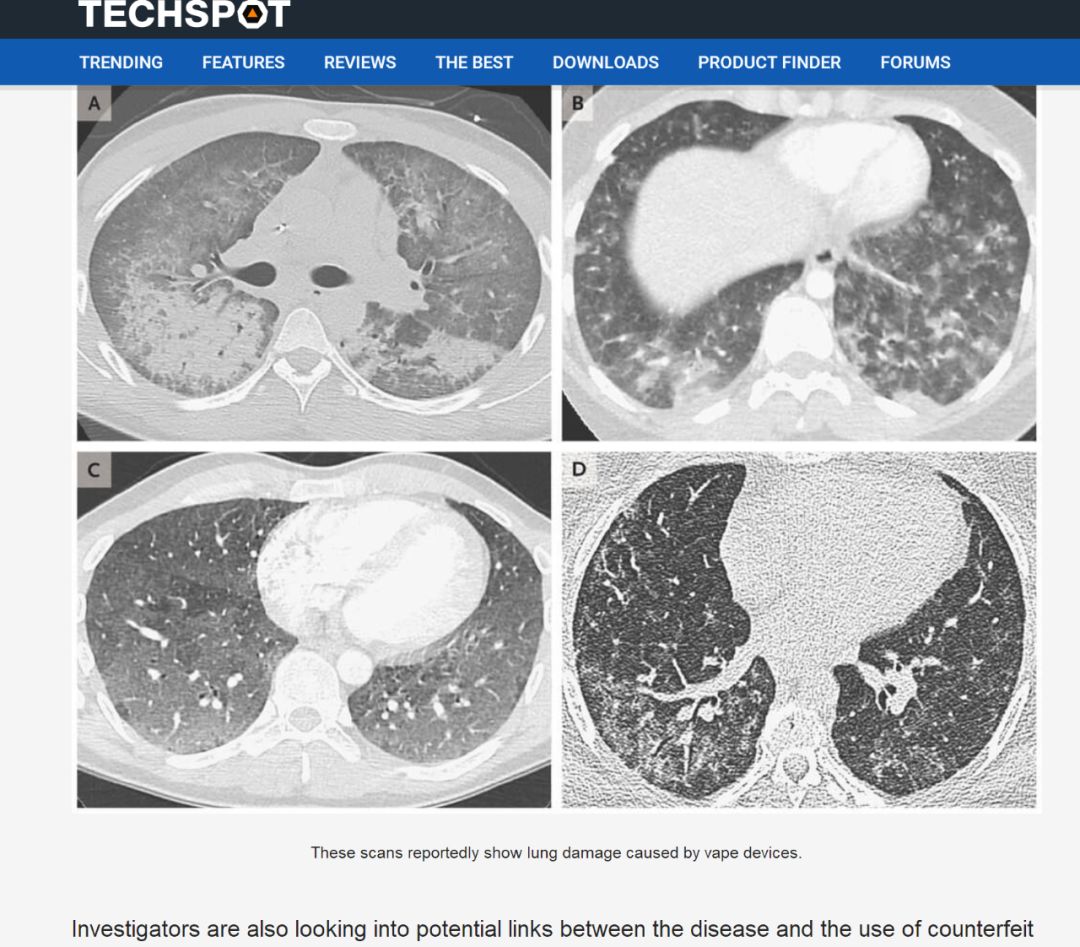

2019年9月美国电子烟肺炎案例

美国医生挖坟发现2019年9月美国电子烟肺炎的案例,经和中国武汉专家交流,确认就是“新冠肺炎”。

https://www.techspot.com/news/81793-deadly-vaping-related-lung-disease-claims-lives-four.html

注意报道的发布时间。